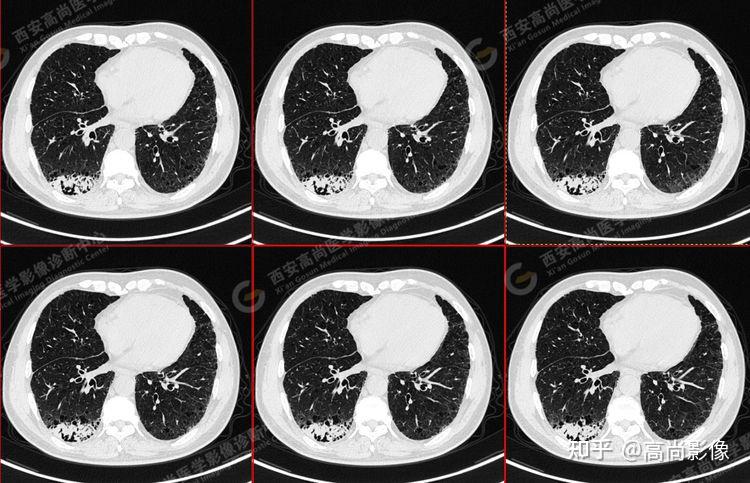

女,63岁,肺粘液腺癌一例